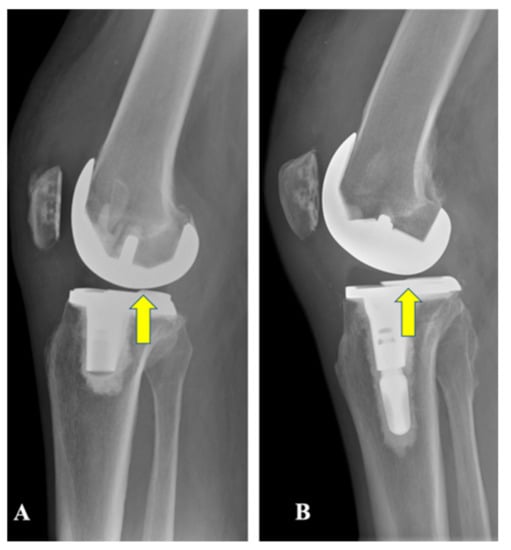

- Stramazzo, L.; Bassi, N.; Ghirardelli, S.; Amoroso, T.; Osti, L.; Indelli, P.F. Posterior stability in posterior-stabilized vs medially congruent total knee replacement: A radiological comparison of two polyethylene designs in a single model. J. Orthop. Trauma Rehabil. 2020. [CrossRef]